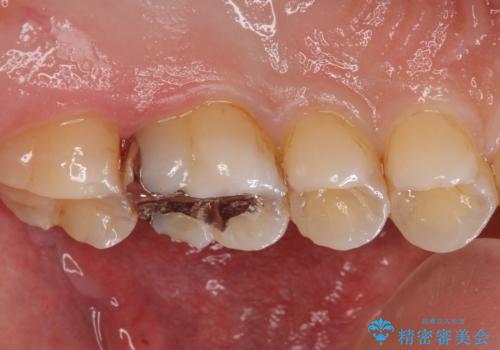

- 銀の詰め物を白くしたいとの事で来院。

奥の歯と歯の間に虫歯ができていました。

また、歯の外側に古いプラスチックの樹脂で治療されていて劣化していました。

なので詰め物のやりかえだけだと外側を覆うことはできないため被せ物で治療しました。

隣の歯も外側に古いプラスチック樹脂があり、詰め物だと覆えないため被せ物で治療を行いました。